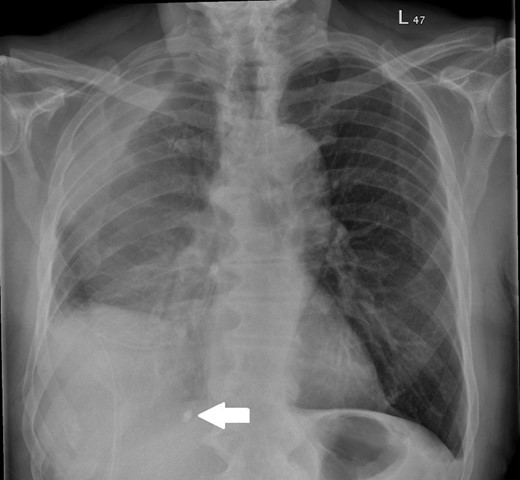

On assessment, he was found to have a right-sided pleural effusion and a right-sided 18 Fr Seldinger drain was inserted for diagnostic and therapeutic purposes. The insertion was difficult so the drain was withdrawn over the guidewire and removed. At this point, it was noted that the tip of the drain was missing. The patient was informed about this, retrieval of the foreign object was not attempted and the event was clearly documented. A new Seldinger drain was placed and the missing drain tip was visible on chest radiograph, see Fig. 1. Cessation of fluid output prompted drain removal and a computed tomography (CT) scan of the thorax was performed to further assess the pleural disease; this showed a large persistent multiloculated effusion.

Following the CT scan, the patient was transferred to a specialist thoracic surgery unit and proceeded to urgent right thoracotomy and decortication for the loculated effusion with removal of the foreign body. Video-assisted thoracoscopic surgery (VATS) was not possible due to the presence of adhesions from previous surgery. The 1-cm drain tip was identified medial to the 12th rib in the posterior cardiophrenic angle and removed. The drain tip following removal is shown in Fig. 2. The patient required transfusion of two units of packed red cells for a low haemoglobin post-operatively but otherwise made a good recovery.